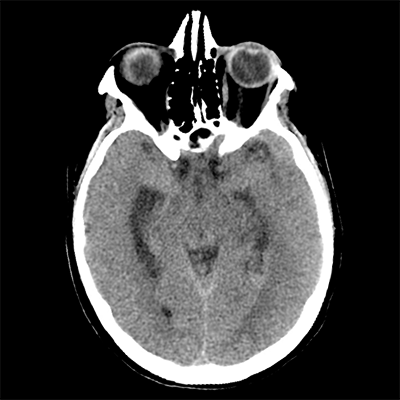

You arrive at the patient's room. You quickly examine her. Her left pupil is truly dilated and unreactive. Her right pupil is also dilated and unreactive, and also deviates to the right. She is unable to follow commands but is moving her extremities spontaneously. The right side of her body seems to be moving slightly less than her left. You escort the patient with RRT and your neurology colleague to radiology, where a non-contrast head CT and CTA head/neck are obtained.

The non-contrast head CT looks generally similar to her prior scan. There's no new hemorrhage anywhere. There's no mass effect causing midbrain compression. The vessel imaging also looks unrevealing-- a slightly hypoplastic right A1 segment, but no clear LVO in either the anterior or posterior circulation. There's no vasoconstriction.